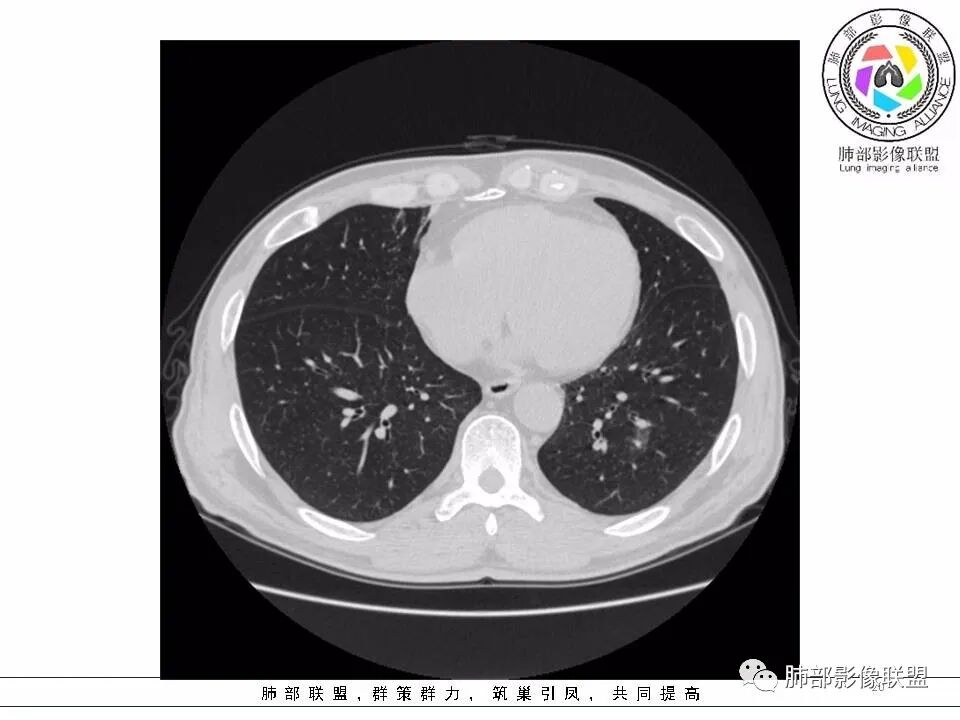

【每日晨读】黄色预警--警惕囊腔型的病变

左肺下叶囊腔,壁厚薄不均,可见磨玻璃成分!考虑恶性可能,腺癌?

左下肺囊性病变,边界不规则,有磨玻璃,内分隔,壁厚薄不均,内有壁结节,考虑囊腔样腺癌。

男性,发热,肿瘤标志物不高,影像:左下肺类圆形囊腔,内有丝丝缕缕,周边有渗出,右肺少许条索,第一印象:囊腔型腺癌

老年男性,左肺下叶囊腔,与临近支气管关系紧密,壁厚薄不均,周围可见实性成分,腔内密度不均匀,可见索条及结节,考虑囊腔型肺癌

男性患者,左肺下叶囊性病变,壁厚薄不均,部分壁较厚,周围可见磨玻璃影,考虑周围型肺癌,腺癌可能。

左下肺囊性病变,边界不规则,周围见磨玻璃影,内分隔,壁厚薄不均,考虑囊腔样腺癌可能性大,鉴别肺大泡合并感染,首次发现建议至少复查一次看看。

中年男性,发热伴咳少量白痰,左下肺可见一囊性空腔,壁厚薄不均,局部周围GGO,边界较清,内见分隔及结节,常规考虑囊腔性腺癌

间断发热半月余。半月前无明显诱因出现发热,体温波动于38℃,畏寒,轻咳,少量白痰,时有活动后胸闷气喘。无胸痛、心慌、乏力、盗汗、消瘦、咯血。于当地诊所予以头孢静脉输注一周,体温正常3天后再次出现体温升高。波动于37.2℃。实验室检查没有太多的问题。左肺下叶囊腔病变,壁比较薄,部分环壁局限性的增厚,边界毛糙,略显模糊,并见与支气管相连,未见明显的壁结节,而囊壁内见丝丝缕缕的索状影。考虑良性病变,毛霉菌感染或隐形性感染,鉴别寄生虫肺部感染。

2.左肺下叶外基底段囊腔样病灶,轮廓柔和,壁厚薄不均,见壁结节。内见分隔或脊状突起。腔内见血管穿行。

这是有“故事”的囊!

3.囊壁外环以磨玻璃影,边界较清楚。

1.囊腔壁厚薄不均,壁结节,内有分隔,其内有血管穿行,指向新生物。

2.临近有边界清楚磨玻璃影,指向腺癌。